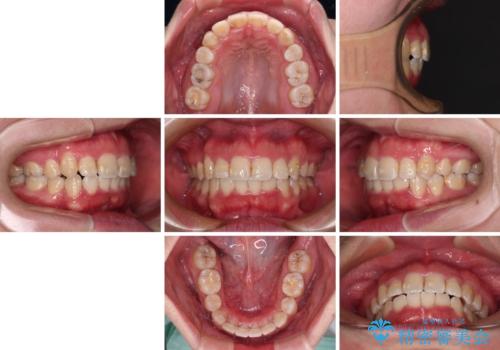

- 矯正装置

- クリアブラケット

- 治療期間

- 1年7ヶ月

- 治療計画

- 上下の八重歯やデコボコを気にして来院された患者様です。

上下ともに八重歯が顕著であったので、上下左右第一小臼歯4本を抜歯し、補助装置を使用して速やかに改善しながら、ワイヤー装置にて矯正治療を行うこととしました。

気になっていた八重歯は装置装着から3か月ほどで解消されました。

2年以内を目標として治療を開始しましたが、1年半ほどで終えることができました。